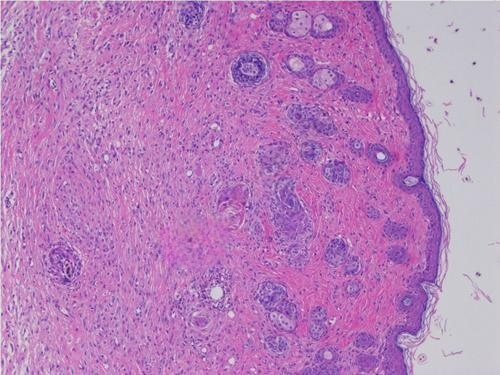

2.小鼠皮肤损伤HE